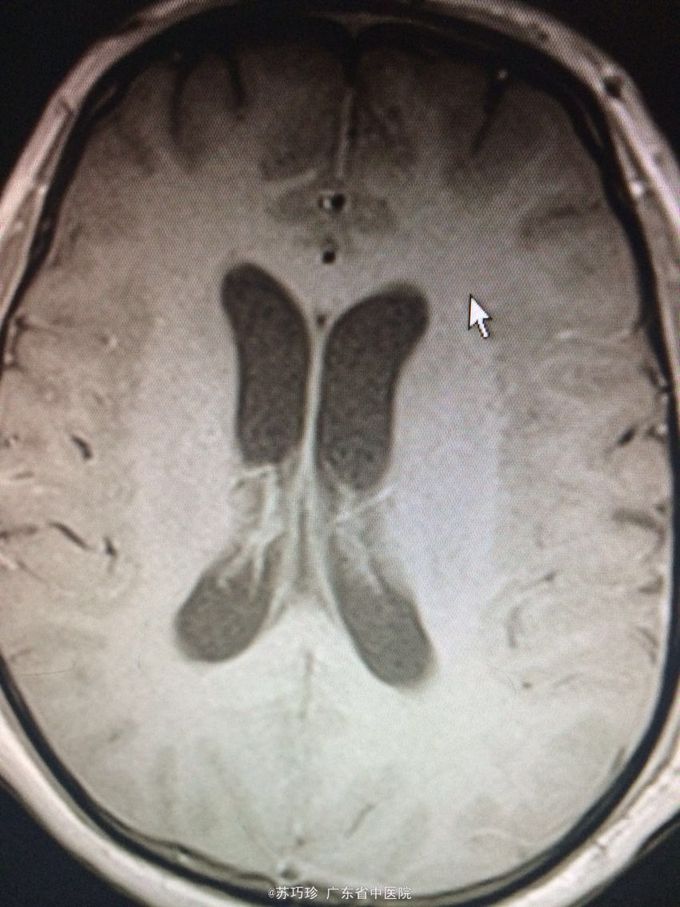

查体:心肺腹(-)。视物重影,右眼外展不到位,T8以下痛、触觉减退,右上肢肌力4级,双下肢肌力0-1级,双下肢肌张力降低,双下肢腱反射消失,腹壁反射消失,颈抵抗约3横指,克氏征(+)。 辅助检查:血常规、肝肾功能及心电图、腹部B超检查未见异常。胸部CT+增强:左肺上叶下舌段慢性炎症;双侧少量胸腔积液,双肺下叶含气不全。头颅+胸椎+腰椎MR平扫+增强:双侧额顶颞枕叶脑沟、双侧侧脑室室管膜、双侧小脑半球软脑膜、脑干软脑膜、颈胸腰段脊髓软脑膜、马尾异常强化影,结合临床考虑炎症性病变;左侧颞叶、左侧丘脑、左侧内囊后肢异常弥散,提示急性脑梗塞灶与感染灶相鉴别,建议复查;脑室系统改变,考虑脑积水;T7/8椎间盘变性,邻近椎体许莫氏结节形成;胸腰椎骨质信号未见异常;骶管囊肿。心脏彩超:EF:64%,主动脉瓣少量返流,左室顺应性减退,少量心包积液。